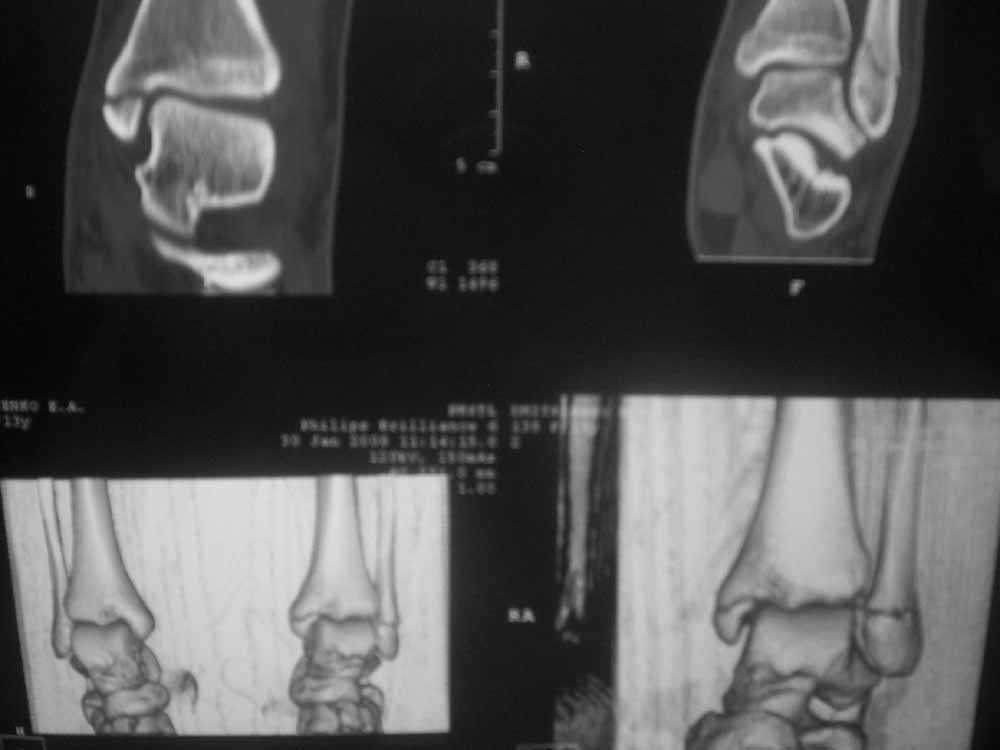

Уважаемые коллеги!Помогите, пожалуйста, советом! Пациентка 14 лет. Двухлодыжечный перелом с (как нам кажется) повреждением межберцового синдесмоза. Вопрос один: оперировать или оставить "как есть" в гипсе? Не будет ли в дальнейшем проблем с суставом. Заранее спасибо.

КТ это очень хорошо. В данной ситуации КТ не помогает а ставит новые вопросы... На мой взгляд проблема в синдесмозе: нужно исключить его расхождени - сделать снимок здоровой конечности. В этом плане МРТ еще круче - при исследовании свежего повреждения коленного сустава всегда найдутся показания к операции.

Уважаемый Сергей! Я не навязываю свое мнение, но по моему, ребенка в данном случае нужно лечить консервативно в гипсовой повязке. Старая мудрость "Хирург славен не теми операциями которые он сделал, а теми от которых он отказался" На мой взгляд по тем снимкам которые представлены, суставная щель по ширине одинакова по всему суставу, значит "вилка" удерживающая таранную кость не разошлась. С уважением Евгений.